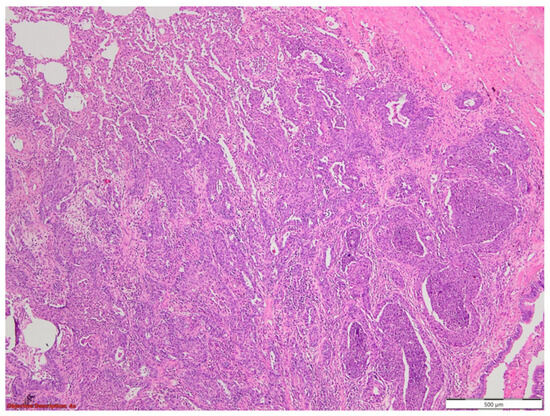

3.1. Case No. 1

3.2. Case No. 2

3.3. Case No. 3

3.4. Case No. 4

4.2.1. Acantholitic Features in Lung Carcinoma

4.2.2. Pseudoangiosarcomatous Feature in Lung Carcinoma

4.2.3. Signet Ring Features in Lung Carcinoma

4.2.4. Clear Cell Features in Lung Carcinoma